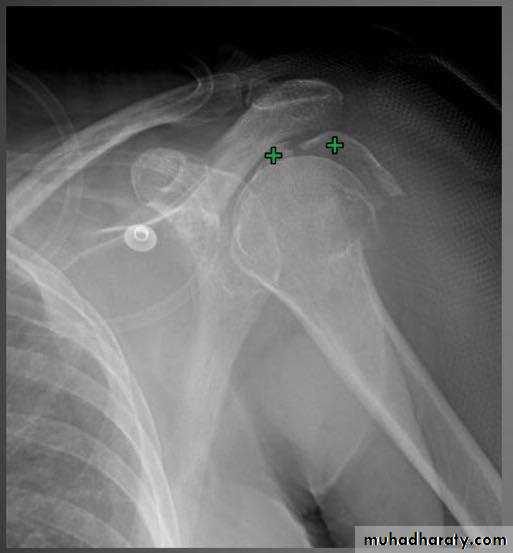

X RAY

10